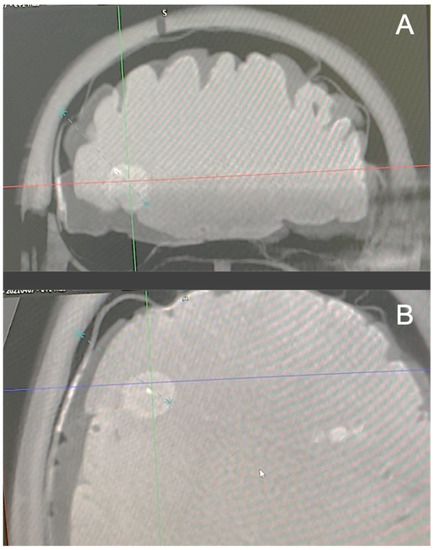

2.2. Surgical Procedure